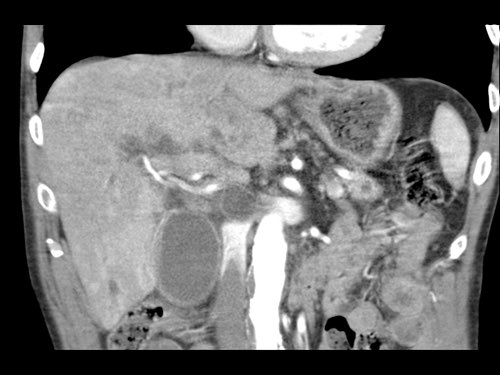

CT axial cho thấy:

- Khối u ở thân tụy (đầu mũi tên trắng).

- Tiếp xúc khu trú < 90º với động mạch mạc treo tràng trên (SMA).

- Tiếp xúc rộng hơn từ 90º – 180º với SMV, SMV bị hẹp nhẹ và biến dạng (mũi tên vàng).

- Giãn ống tụy

Tái tạo mặt phẳng coronal cho thấy:

- Bất thường bờ viền thành SMV được nhận thấy rõ hơn trên tái tạo coronal này (mũi tên).

- Huyết khối trong các nhánh bên của SMV (mũi tên xanh nhỏ).